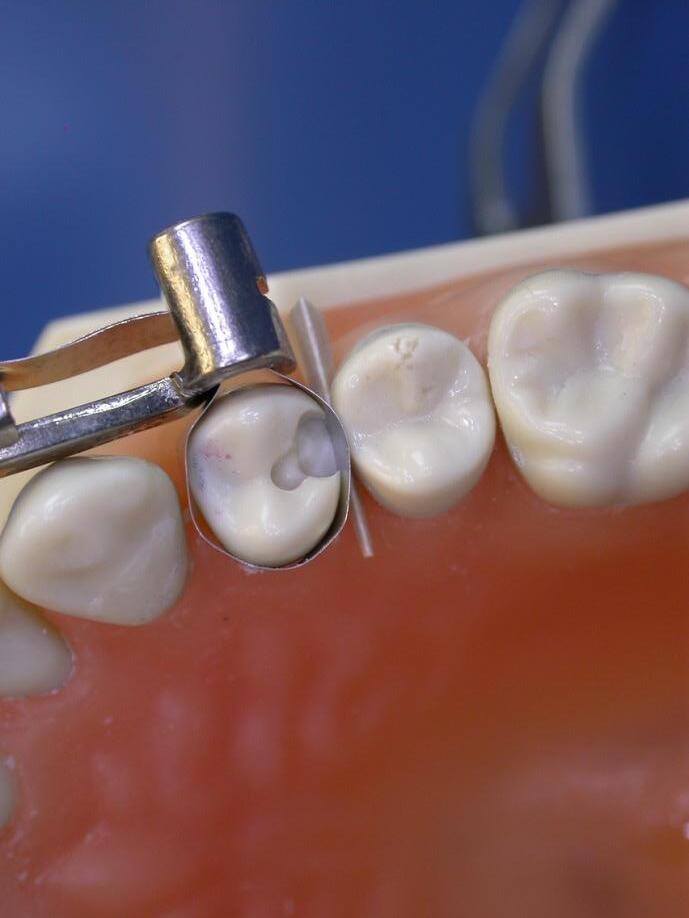

Hall techniek, prepareren, pulpotomie en pulpectomie

Lisa van 3 jaar oud komt binnen in jouw behandelkamer. Haar ouders geven aan dat ze sinds enkele dagen last heeft als ze aan het eten is. Lisa is nog nooit eerder bij de tandarts geweest en laat het nog niet zo goed zien. Spelenderwijs krijg je het voor elkaar toch in haar mond te kunnen kijken en je ziet een grote occlusale caviteit in element 85.

Tja, hoe nu te handelen? Er zijn verschillende behandelopties. Ga je vullen of toch iets anders doen?

Deze 1-daagse cursus zal nader in gaan op de behandeloptie ‘the seal is the deal’ met behulp van roestvrijstalen kronen (hierna genoemd RVSK). Wanneer plaats je een RVSK en wanneer juist niet? Welke methoden zijn er? En mocht er toevallig sprake zijn van een goede coöperatie en je hebt een duidelijk röntgenbeeld, welke opties zijn er dan met betrekking tot een endodontische behandeling in het melkgebit?

De cursus zal gericht zijn op zowel de theoretische als de praktische kant. Je hebt uitgebreid de tijd om hands-on te oefenen.